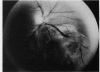

Beading of a retinal vein draining a choroidal melanoma is reported, showing that the endothelial proliferation producing the beading is a response to some blood borne factor(s) traversing the vein and that retinal capillary non-perfusion adjacent to the beaded vein is not a necessary part of the process.